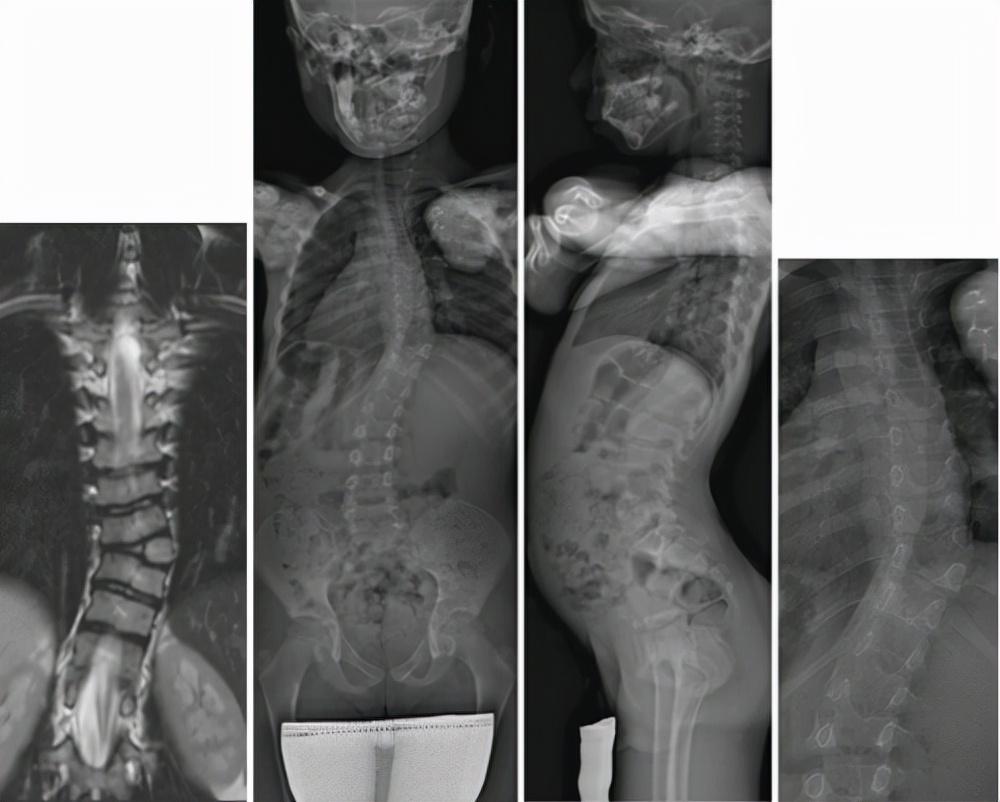

最常见的临床表现就是患者会出现 脊柱侧凸的现象 ,一般从后方去看的时候,我们可以看到正常人的脊柱处于一条直线,但是对于患者来说,可以 明显 的看到脊柱有侧凸的现象,所以如果发现 孩子 在很小的时候就有此种情况的话,一定要加以重视,及早进行干预才可以将情况尽快的控制起来,否则, 脊柱侧侧突 的情况可能会变的愈加的严重,患者的情况也会受到相应的影响,一定要关注脊柱侧突的问题,才能够尽早找到 病因 。

通过X线检查可以 初步的了解 到患者的脊柱情况,如果进行X线检查的时候发现孩子的脊柱存在异样的话,那么,要查找其 出现的原因 才能够知道如何做出相应的干预。脊柱对于身体内的 脏器 以及外观都起着较为关键的作用,所以需要对其进行关注才能够选对方式来进行控制,否则势必会因为脊柱的意义而影响到患者的 日常生活 和心理方面的情况。